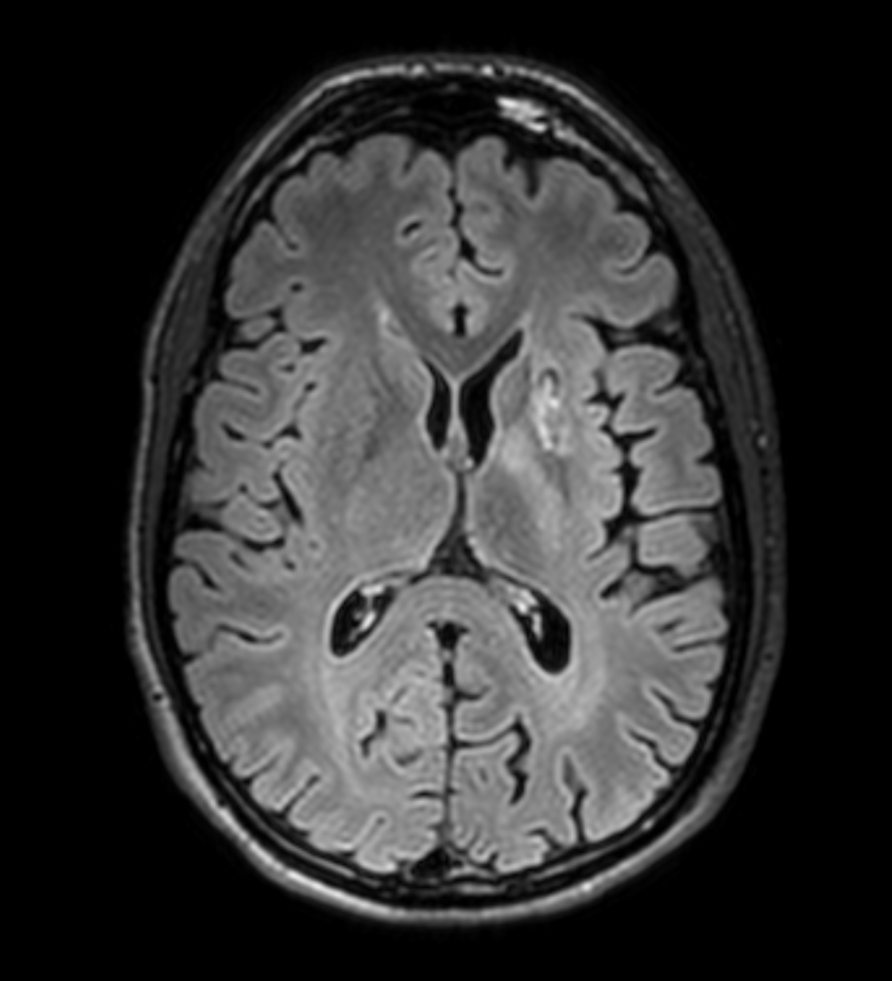

3D VIEW - T2w FLAIR